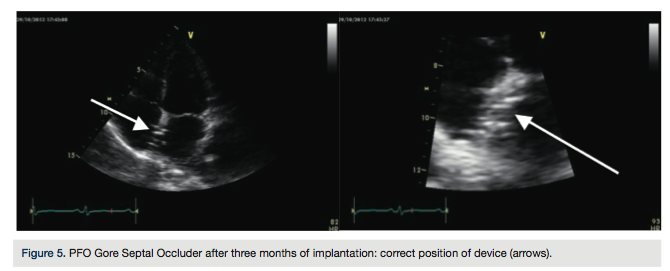

Transthoracic echocardiography the following day confirmed no residual shunt and correct position of device.

months). Follow-up echocardiogram at three months demostrated no residual shunt through the fenestretion and a well-positioned device (Figure 5). The patient remains free of other neurological events and migraine.